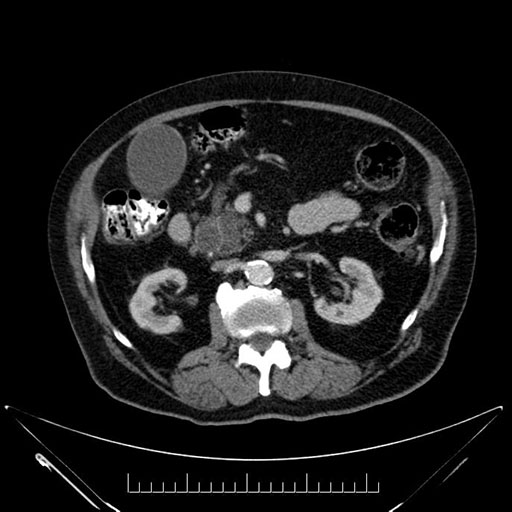

Axial - 3 months prior